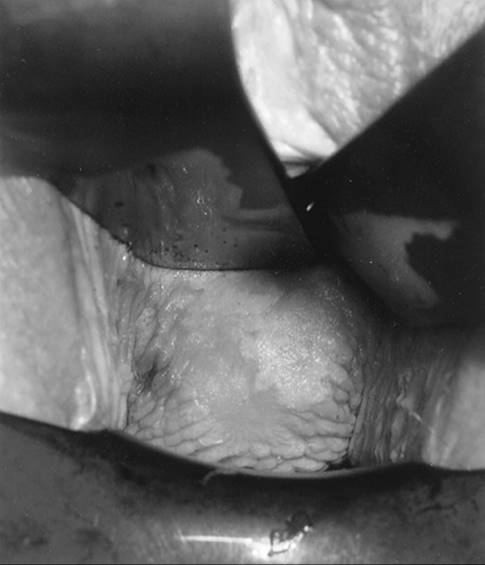

Patients with VIN most commonly present with pruritis and vulvar lesions. These lesions may appear scaly, white, red, or hyperpigmented (Fig. 51.1, Fig. 51.2, Fig. 51.3 and Fig. 51.4). Careful inspection with 5% acetic acid and liberal use of punch biopsy are the cornerstones of diagnosis. An underlying malignancy may be present in 7% to 22% of patients who undergo surgical excision for vulvar carcinoma in situ. Wide local excision with at least a 5-mm margin is the preferred management option as it allows pathologic confirmation and is associated with less morbidity than skinning vulvectomy. Skinning vulvectomy with split thickness skin graft may be an option in patients with widespread disease. Laser ablation is also an effective nonmutilating option in patients with multifocal or clitoral disease. Recurrences are frequent (10%–50%) despite negative surgical margins and therapy should be tailored to symptom control and ruling out underlying malignancy. Patients should be followed every few months with careful visual inspection of the vulva and taught self-exam skills as well.

FIG. 51.2. Vulvar carcinoma in situ before application of 5% acetic acid. See color figure 51.2.

FIG. 51.3. Vulvar carcinoma in situ after application of 5% acetic acid. See color figure 51.3.